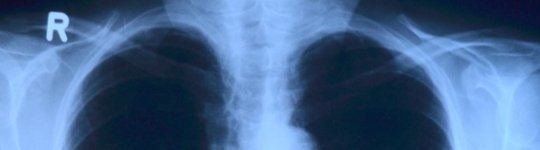

a) Sóc tècnic en imatge per al diagnòstic. A part de fer radiografies, també fem altres proves d'imatge, com TC. Però el que més estic fent aquests dies són totes les radiografies toràciques als pacients amb sospita o confirmats de COVID-19 a l'Hospital Universitari Arnau de Vilanova. També realitzem radiografies als pacients lliures de símptomes de COVID-19 però amb un volum més reduït. La meva jornada s'ha vist modificada, ja que, hem fet equips perquè no estiguem exposats tots alhora. Hi ha gent que pertany a un equip, gent que a dos i gent que està a tots. És una mica complicat, igual que la situació que estem vivint.